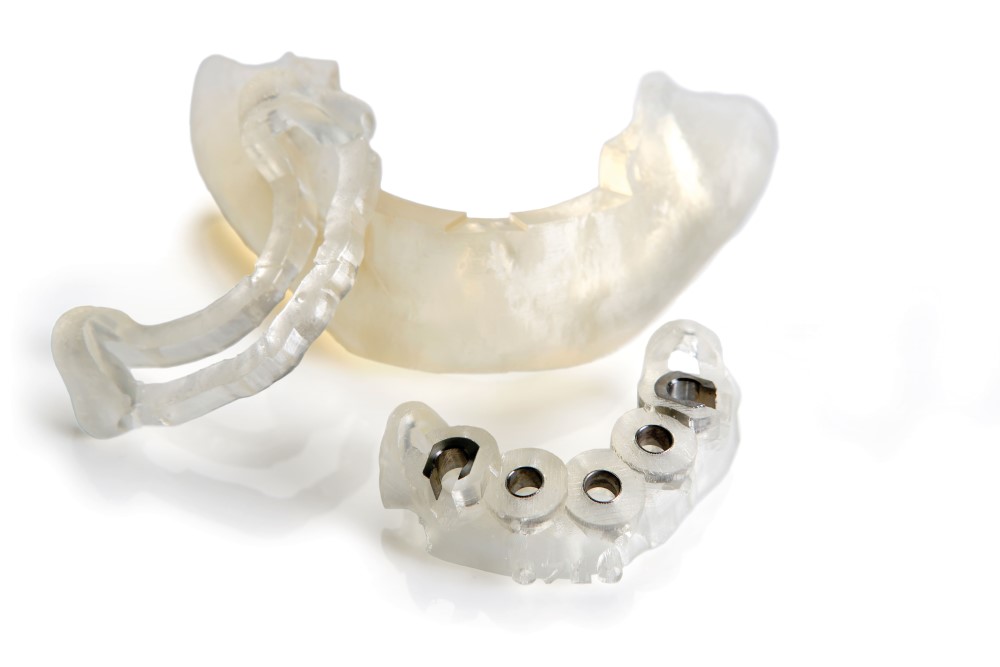

サージカルガイド

サージカルガイドとは、インプラント手術用のマウスピース型装置です。

ドリルを固定する穴があいているため、歯肉を大きく切り開く必要がなく、インプラントを埋入する位置や深さ、角度のズレをほぼなくすことができます。

安全性への配慮に加え、インプラント治療の精度向上のため、当院ではサージカルガイドを導入しております。